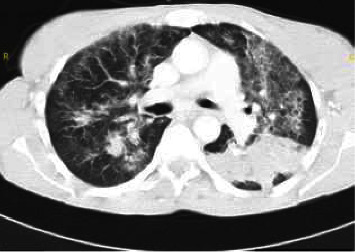

Rhodococcus equi is a rare human opportunistic pathogen that has been increasingly reported in recent decades. It mainly affects immunosuppressed patients, and in particular human immunodeficiency virus (HIV)-infected patients, where it typically presents as cavitary pneumonia. Early treatment with combined and effective antimicrobials and antiretroviral therapy after prompt diagnosis is essential to ensure an optimal outcome. We present a case series of three human Rhodococcus equi infections in HIV-infected patients with advanced immune suppression, treated at the University Hospital of Antwerp, Belgium.

Abstract Image